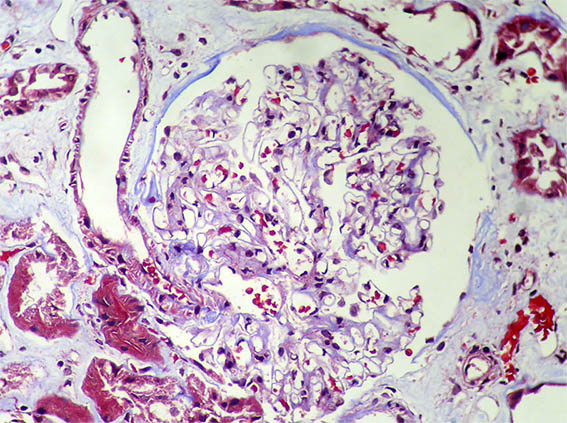

Figura 9. Plata-metenamina, X400.